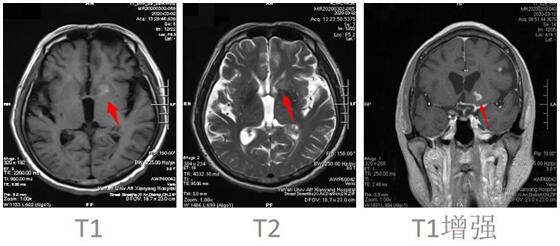

患者邱某,男,67歲 ,因“反復低熱頭痛40余天”入住我院神經內科三病區(qū),入院后行神經系統(tǒng)體格檢查示:表情淡漠,腦膜刺激征陽性;行顱腦磁共振增強掃描示:顱內可見多發(fā)點狀及小片狀結節(jié)灶,增強掃描呈小片狀及環(huán)形明顯強化,考慮①感染性病變,結核性腦膜炎可能,②轉移瘤待排:請結合臨床實驗室檢查;行腰椎穿刺術示:顱內壓310mmH2O,潘氏試驗陽性,并于腦脊液中檢測出結核分枝桿菌(咸陽市首例)。腦脊液常規(guī):淡黃色清亮,白細胞計數(shù) 210*106/L,潘氏試驗陽性,中性粒細胞比率 90.0%。腦脊液生化:葡萄糖 1.40mmoI/L,氯 105.5mmol/L,微量總蛋白 2749mg/L,陳萍主任醫(yī)師、代昌飛副主任醫(yī)師及科室其他醫(yī)師慎重討論后考慮:結核性腦膜炎,并立即制定抗結核、降低顱內壓、抑制腦水腫、減輕炎癥反應等相關治療方案。王寶艷護士長指導護理應加強護理,早期康復。經討論匯總,為該患者制定特色治療方案,動態(tài)調整,密切觀察。在科室醫(yī)生護士的精誠協(xié)作下,患者渡過險關。復查腰椎穿刺術:初壓:170mmH20,常規(guī):潘氏試驗陽性;白細胞計數(shù) 120*106/L。淋巴細胞百分率 10.0%,中性粒細胞百分率 90.0%。生化:微量總蛋白 1503mg/L。出院后繼續(xù)抗結核治療。